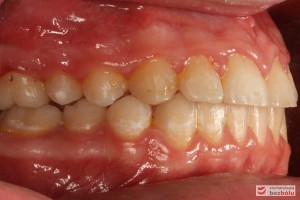

Rodzice zgłosili się z pacjentem celem rutynowej kontroli ortodontycznej. Wykonano OPG i po analizie modeli diagnostycznych stwierdzono brak miejsca dla wyrzynania dolnej prawej piątki stałej oraz zwężenie szczęki wraz z rotacją górnych zębów szóstych. W łuku górnym w pierwszym etapie leczenia zastosowano Rotator, celem odrotowania 6-tek stałych oraz ekspansji łuku w wymiarze poprzecznym. Następnie zamontowano aparat stały metalowy do uszeregowania zębów w łuku. W łuku dolnym miejsce odtwarzano stosując aparat stały i odpowiednią mechanikę leczenia. Leczenie aktywne trwało 3,5 roku, po czym zastosowano terapię retencyjną (retainer stały w żuchwie oraz Płytkę Hawley’a w szczęce).